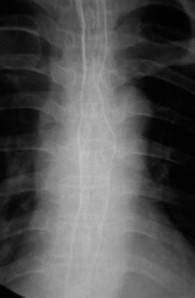

女,51岁,以“进行性吞咽困难1年”为主诉于2007年2月19日入院。钡餐造影、胃镜示食管上段占位性病变,确诊为食道鳞癌(图1),拒绝手术,行放疗+今又生治疗。食道镜下瘤内注射今又生,1×1012VP/次/周×6,放疗在今又生注射3 d后开始,采用常规分割三野等中心照射,剂量65cGY。治疗结束后4周,食管X线、胸部CT显示肿瘤完全消退(图4-5)。

放疗65GY +今又生6支后